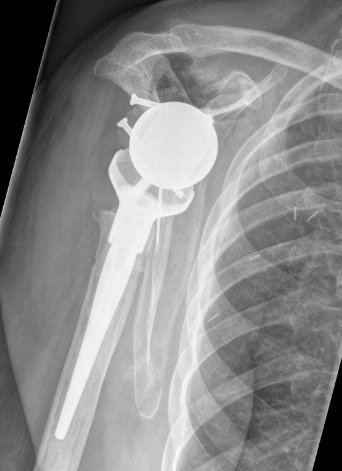

Revise to

- aTSA

- rTSA

- hemiarthroplasty